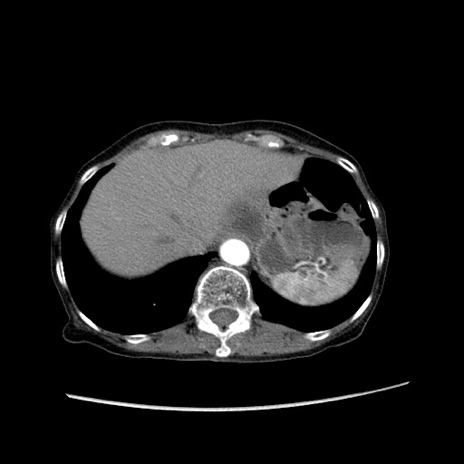

冠状断像

【症例】80歳代女性

【主訴】胸のつかえ感

【現病歴】約9時間前に食後から胸のつかえた感じあり、嘔吐あり、来院。

【既往歴】胃癌(全摘)、胆摘、虫垂炎

【身体所見】心窩部に圧痛あり、反跳痛なし。

【データ】WBC 5700、CRP 0.05